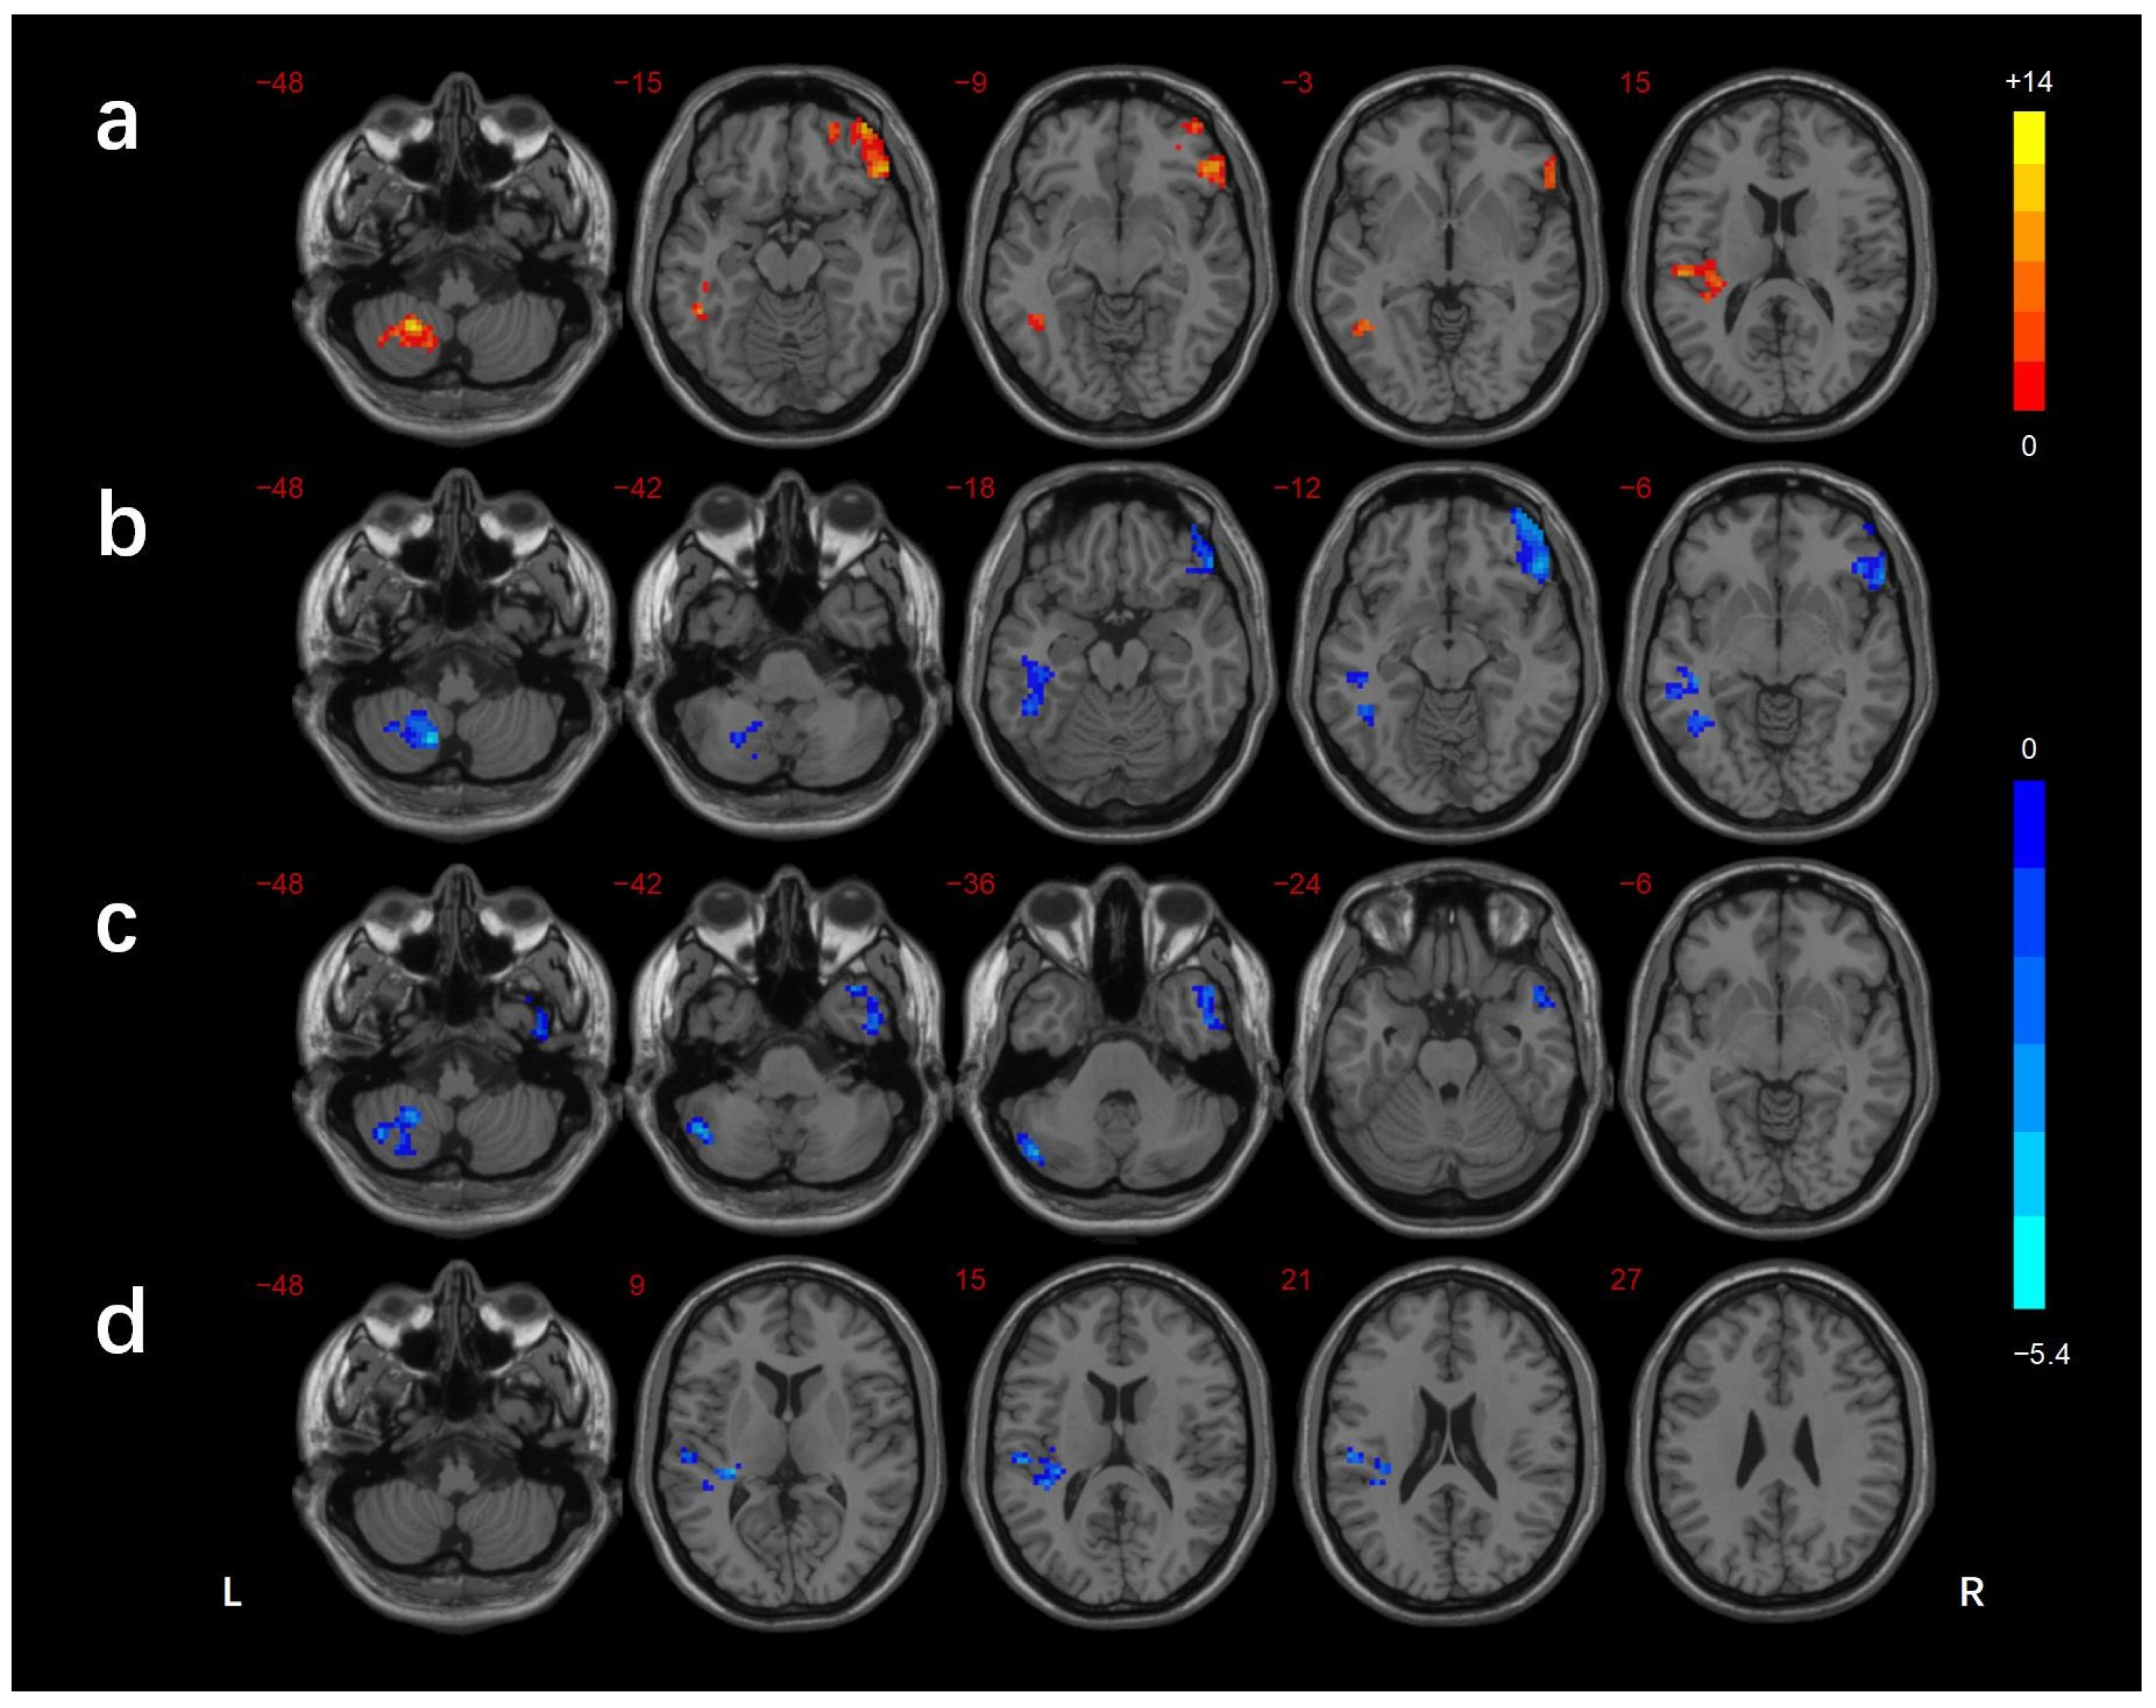

3.2. FCD Analysis

| Brain Regions | BA | Voxels (mm3) | Peak MNI Coordinates | f/t-Value | ||

|---|---|---|---|---|---|---|

| X | Y | Z | ||||

| ANOVA | ||||||

| L_cerebellar lobule VIII/Crus II | - | 104 | −24 | −54 | −48 | 13.916 |

| L_ITG/FG | 37 | 109 | −39 | −51 | −6 | 12.070 |

| R_IFG | 47 | 217 | 51 | 33 | −12 | 13.389 |

| L_STG | 13/41 | 116 | −36 | −30 | 9 | 12.689 |

| DMCN vs. HC | ||||||

| L_cerebellar lobule VIII/Crus I/II | - | 159 | −48 | −72 | −33 | −4.836 |

| R_ MTG/ITG | 38/21 | 175 | 51 | 12 | −30 | −4.089 |

| DMCI vs. HC | ||||||

| L_cerebellar lobule VIII | - | 125 | −15 | −63 | −48 | −5.304 |

| L_MTG/ITG/FG | 37 | 245 | −45 | −60 | 0 | −4.382 |

| R_IFG | 47 | 253 | 51 | 33 | −15 | −4.695 |

| DMCI vs. DMCN | ||||||

| L_STG | 41 | 124 | −30 | −30 | 9 | −3.784 |